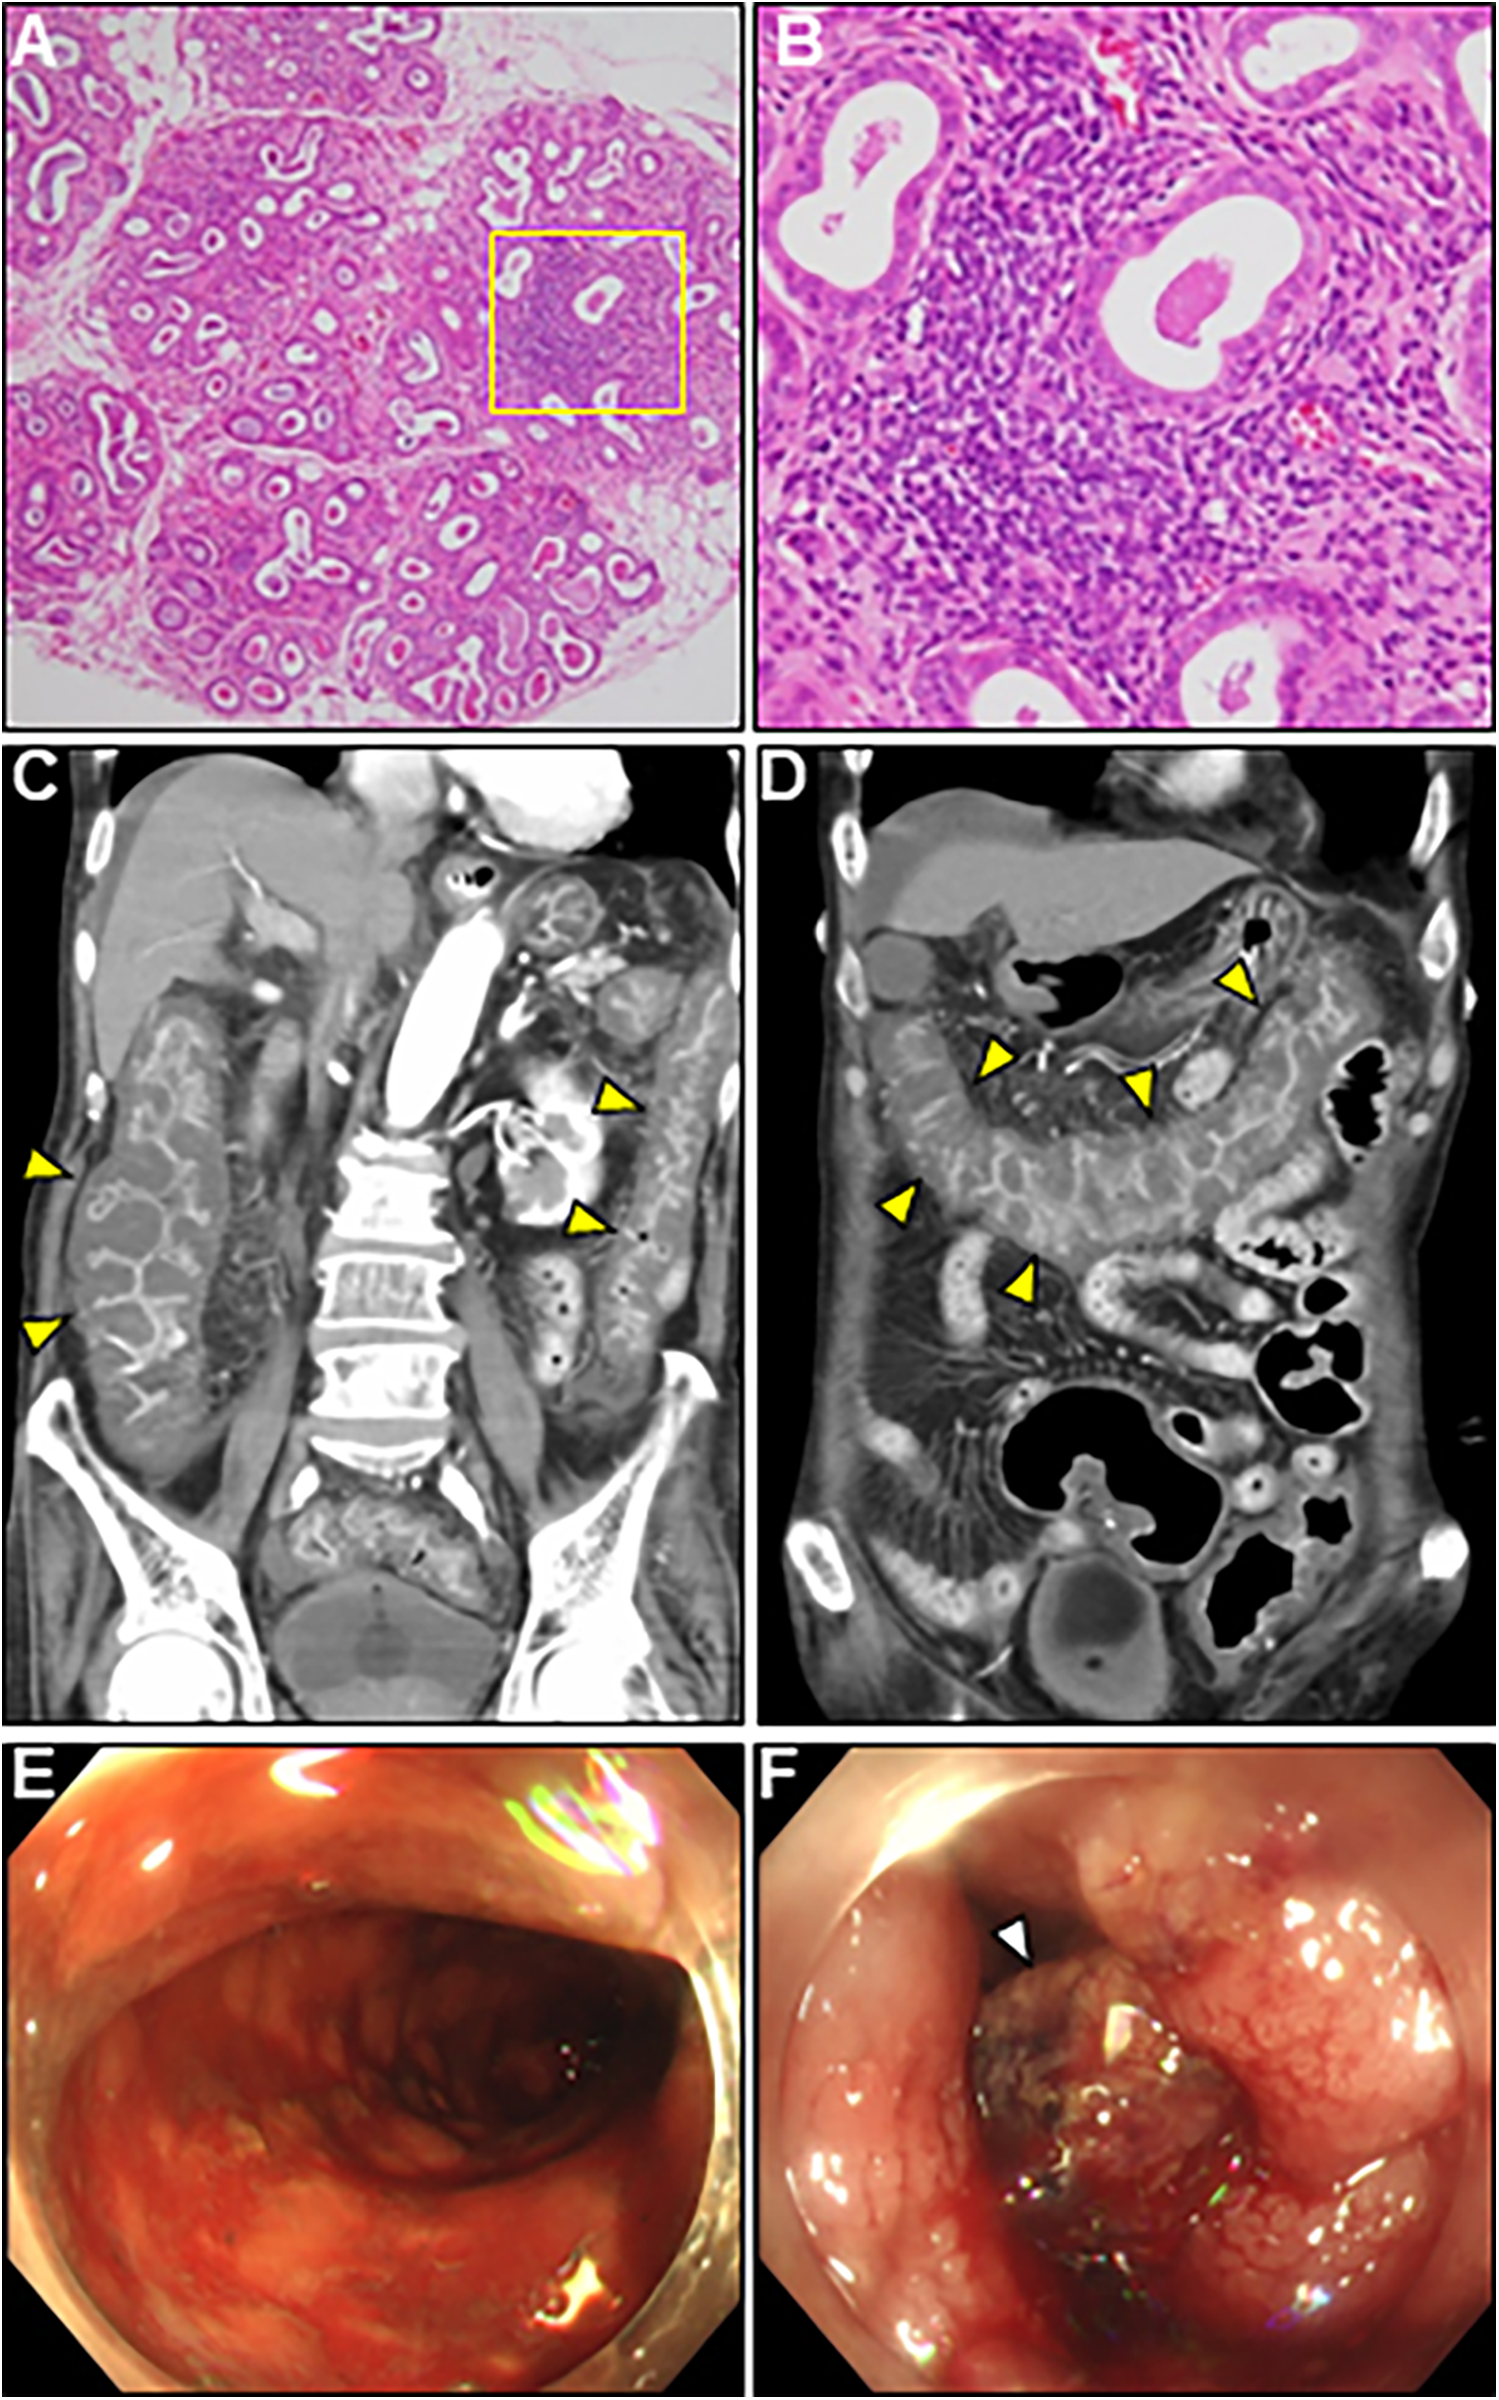

Figure 4. Lip gland histopathology, computed tomography (CT) and colonoscopy findings. (A) Pathology of a minor salivary gland biopsy (20× magnification). (B) Magnified view of the box in (A) at 40×. Hematoxylin and eosin staining showing focal lymphocytic sialadenitis with periductular aggregates of >50 lymphocytes. (C,D) Coronal enhanced CT revealing whole and homogeneous large bowel wall thickening characterized by submucosal edema and mucosal thickening with the disappearance of the haustral folds (arrowheads). Note the intact small bowel. (E,F) Colonoscopy revealed continuous diffuse mucosal inflammation from the rectum to the transverse colon. There are no vascular patterns, multiple ulcers with friability, mucosal desquamation (arrowhead), or contact bleeding.

A comprehensive diagnostic evaluation of eosinophilia, including eosinophilic granulomatosis with polyangiitis, hypereosinophilic syndrome, parasitic infections, and hematological malignancies, revealed negative results. Viral screening using paired serology for virus antibody titers was unremarkable (Supplementary Table S1). In addition, a workup for the unexplained eosinophilia was performed. Most importantly, a renewed interview with the patient's family revealed that the patient complained of oral dryness for >6 months and frequently drank too much liquid. We performed serologic testing for underlying systemic autoimmunity using stored blood samples obtained on admission. Strikingly, serologic testing using pre-corticosteroid treatment sera on admission demonstrated strong positivity for anti-SS-A and anti-SS-B antibodies (469 and 199 U/ml, respectively), strongly suggesting SS. Elevated levels of serum rheumatoid factor (31 IU/ml, normal: < 15 IU/ml), interleukin (IL)-4 (36.5 pg/ml, normal: < 3.9 pg/ml), IL-5 (50.9 pg/ml, normal: < 3.9 pg/ml), and antinuclear antibody titer (1:320) were also noted. Brain CT revealed fatty changes in the bilateral parotid glands. An abnormal Schirmer's test result and lip biopsy of the patient revealed focal lymphocytic sialadenitis with a focus score of ≥1 focus/4 mm2, meeting the 2016 ACR/EULAR classification criteria for pSS (4) (Figures 4A,B). Based on the above, the final diagnosis of AEM associated with pSS was established. On day 22, the patient showed an evident improvement in cardiac functional and structural abnormalities, as well as electrocardiographic findings, except for an LV apical aneurysm (Figures 2G,H; Supplementary Video S3, and S4). A follow-up brain MRI demonstrated complete recovery of AOM. Thereafter, the patient received a maintenance dose of prednisolone (20 mg/day) and underwent cardiac rehabilitation. The post-treatment course of the patient was complicated by digestive involvement (DI) including esophageal candidiasis and chronic atrophic gastritis. Accordingly, oral miconazole and a reduced dose of prednisone (10 mg/day) were prescribed. On day 51, the patient experienced three episodes of bloody stools, and the anticoagulant was discontinued. On day 52, the patient experienced hemorrhagic shock due to lower gastrointestinal bleeding with progressively impaired consciousness, necessitating tracheal intubation, catecholamine administration, frequent blood transfusions, and careful monitoring in the ICU. Enhanced CT showed diffuse, severe, and edematous thickening of the entire colonic wall despite intact mesenteric arterial circulation (Figures 4C,D). Colonoscopy revealed diffuse edematous mucosa, complete loss of vascular pattern, mucosal friability, and multiple superficial ulcers with contact bleeding in the rectum and sigmoid colon (Figures 4E,F). These lesions were observed in continuity with the rectum. Given the patient's underlying condition of pSS, CT and colonoscopy findings suggestive of ulcerative colitis (UC), the rapidly progressive course, and steroid resistance, fulminant UC was strongly suspected. However, we could not perform colon biopsies due to the rapid deterioration of the patient's condition. Despite intensive therapy, the patient eventually succumbed to septic shock on day 59. An autopsy of the patient was not performed because of the refusal by family members. We present a summarized illustration of the case presentation in Supplementary Figure S1.